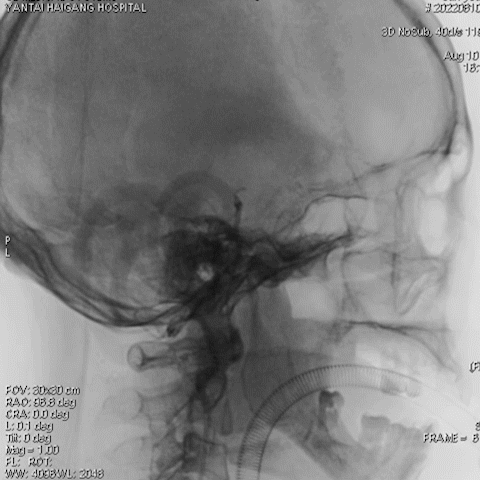

诊断

主要诊断:

1.右侧椎动脉V4段重度狭窄(90%);

2.高血压病2级 高危;

3.小脑梗死。

病变情况分析:右桡动脉穿刺,置6F桡动脉鞘管,5F多功能导管在泥鳅导丝辅助下脑血管造影提示:右椎动脉V4段重度狭窄(约90%)。